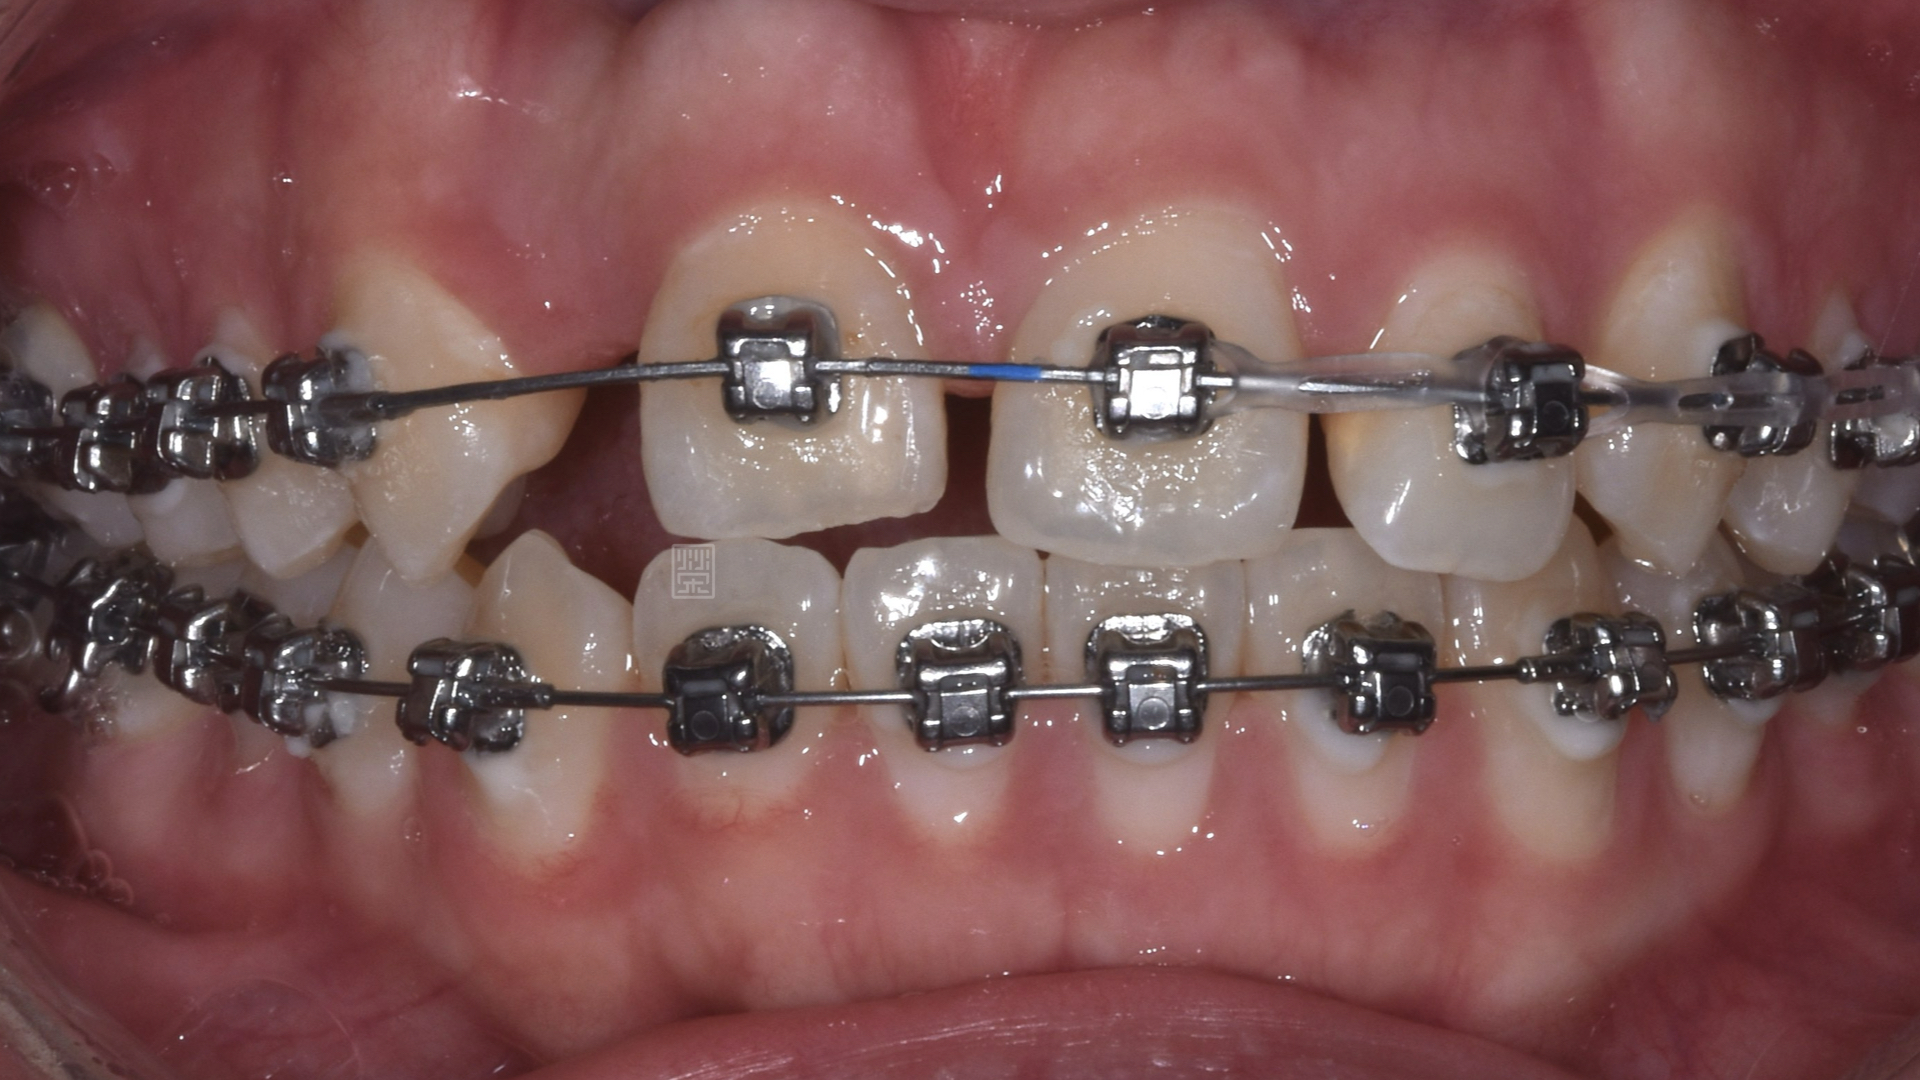

矯正移出側門牙空間

首先張馨文醫師先將牙齒重新排列,但是在門牙的部分因為先前外傷關係,牙齒發生沾黏的狀況,牙齒移動度很小,吳禕凡醫師藉由皮質骨手術加上術後立即施力,將門牙拉至中央位置,並且給側門牙植牙適當空間。